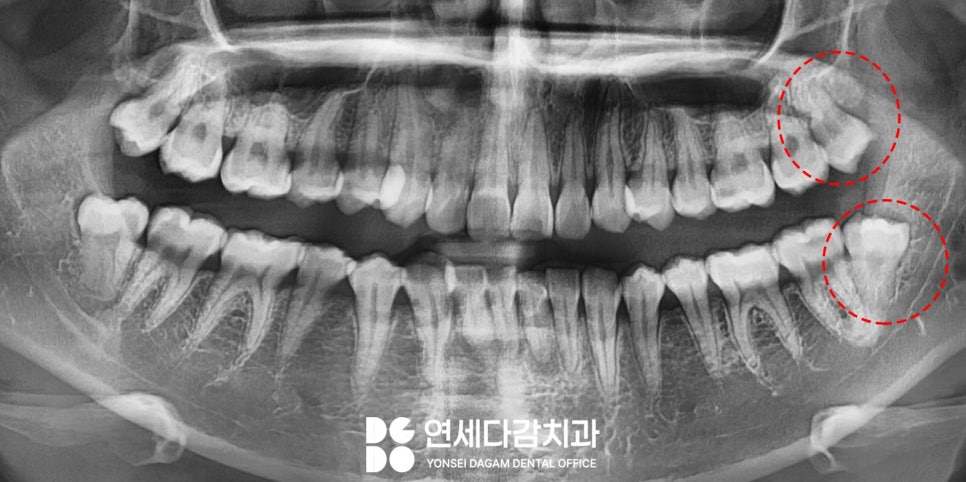

해당 케이스는 사랑니 주변으로

잇몸이 부어서 통증을 호소하고 있었습니다.

오래전부터 문제가 있다는 것을

인지하고 있었으나,

공포감이 심해 그동안 계속

치료를 미루고 있었습니다.

구강 검사 결과,

아래 매복 사랑니 주변으로

특히 심한 부종이 관찰되었으며,

해당 부위를 촉진했을 때

고름이 나오기도 했습니다.

이는 감염(지치주위염)이 진행 중임을

나타내는 명백한 징후였습니다.

추가로 위쪽 사랑니 부위에도

음식물이 자주 끼고,

평소 위생관리에 어려움을 겪고 있었습니다.

또한 어금니 중 하나는

심한 인접면 충치가 발견되었습니다.

먼저 CT를 촬영하여 주변 구조물을

정밀하게 분석한 뒤 발치 계획을 세웠습니다.